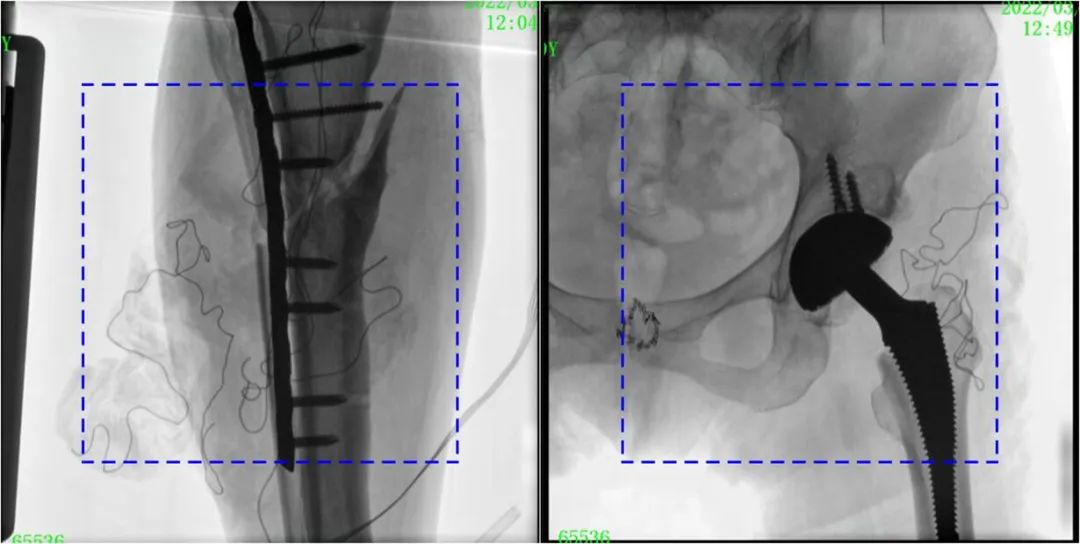

術(shù)中使用普愛醫(yī)療大平板一體式C形臂進行透視,判斷骨折情況及克氏針、髓內(nèi)釘?shù)冉饘僦踩胛锏奈恢茫M行調(diào)整。C形臂準確的術(shù)中定位,大大縮短了手術(shù)的時間,減輕了患者的痛苦,輔助手術(shù)順利完成。

在進行髓內(nèi)釘內(nèi)固定術(shù)時,醫(yī)生需要同時觀察到入釘點和骨折部位的情況,普愛醫(yī)療大平板一體式C形臂采用30CM×30CM的平板探測器,能夠呈現(xiàn)更廣闊的成像面積,滿足大部分長骨髓內(nèi)釘內(nèi)固定術(shù)的攝片需求。

術(shù)中定位準確、出血量少,術(shù)后影像顯示股骨移位糾正,恢復(fù)良好力線,手術(shù)效果良好。

PLX119C臨床圖像與傳統(tǒng)圖像對比

注:藍色虛線內(nèi)為傳統(tǒng)21CM×21CM平板的成像區(qū)域。